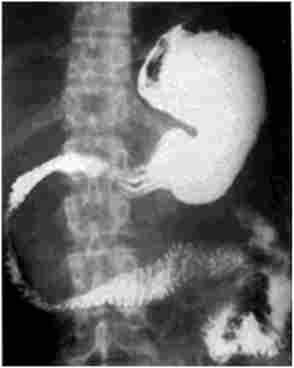

Апаратні та інструментальні методи діагностики. Оглядова рентгенографія черевної порожнини (рис. 20.1) має більше академічне значення в діагностиці ХП, проте характерні зміни вдається виявити лише у хворих з вираженим звапнінням паренхіми залози і (або) досить великими звапнінням конкрементами в панкреатичної протоці.

Оглядова рентгенограма органів черевної порожнини при хронічному кальціфіцірующем панкреатиті

Мал. 20.1. Оглядова рентгенограма органів черевної порожнини при хронічному кальціфіцірующем панкреатиті.

На знімку видно великі кальцинати в проекції підшлункової залози на всьому протязі (вказані стрілками)